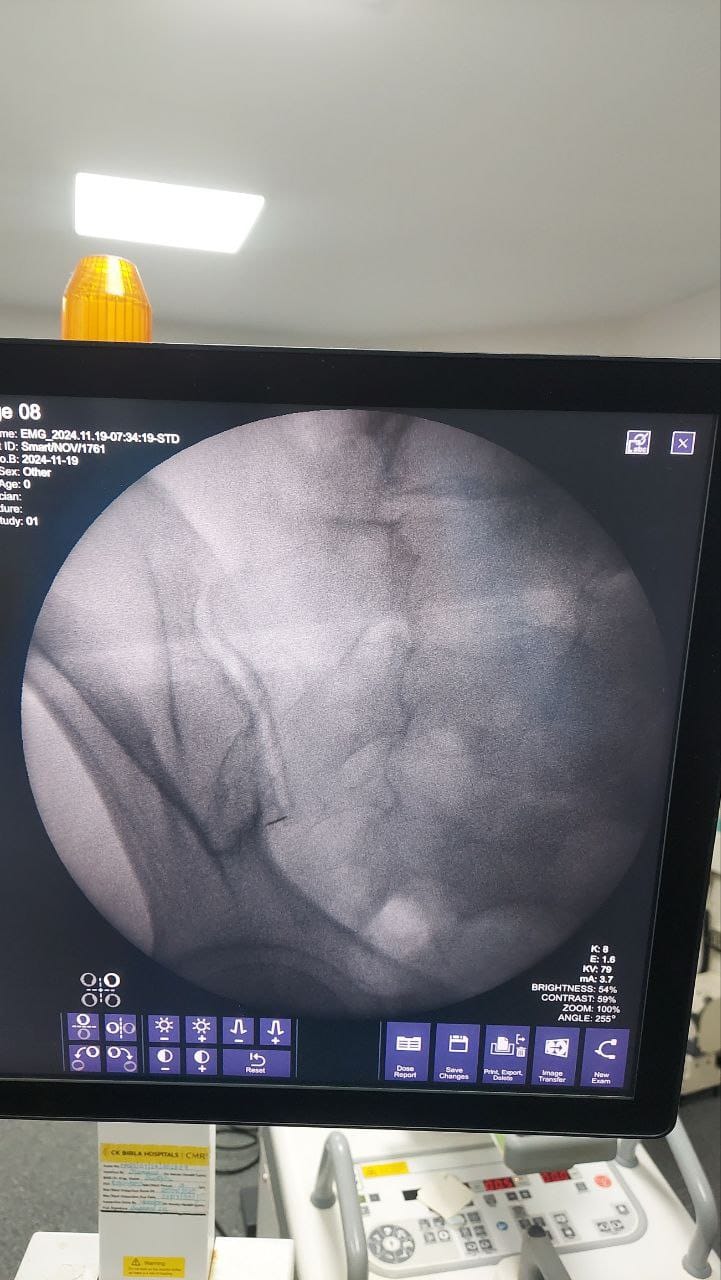

Procedures